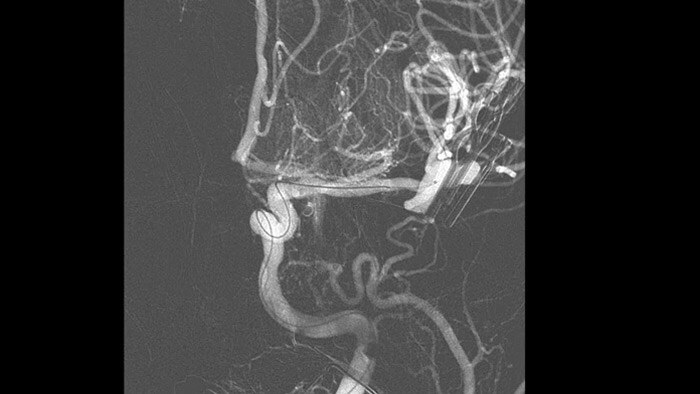

Ver con claridad y navegar de manera eficiente cuando se tratan los aneurismas cerebrales

Los nuevos dispositivos pueden ser difíciles de visualizar cuando se tratan aneurismas cerebrales, lo que puede alargar el tiempo del procedimiento. Eso hace que las excelentes imágenes 2D y 3D sean más importantes que nunca para guiar las decisiones de tratamiento y la colocación del dispositivo, y administrar la dosis de radiación de manera eficiente.

Vea claramente los perforadores cerebrales y los dispositivos desafiantes

SmartCT Vaso IA

Mejorar la vista de los stents endovasculares, los desviadores de flujo y otros dispositivos, así como la morfología de los vasos hasta el nivel del perforador con SmartCT Vaso. Esta técnica de adquisición se basa en una exploración por TC de haz cónico y una inyección de contraste intrarterial. Se utiliza cada vez más para el seguimiento de aneurismas tratados con stents desviadores de flujo para comprobar la posición del dispositivo.

Visualice alteraciones anatomopatológicas complicadas en 3D de alta fidelidad

SmartCT Angio

SmartCT Angio proporciona una vista volumétrica en pocos segundos para ayudar a evaluar la ubicación, el tamaño, el cuello y la gravedad del aneurisma para la planificación del tratamiento. Los volúmenes 3D se ven con alta resolución espacial y compensación automática del movimiento del paciente.